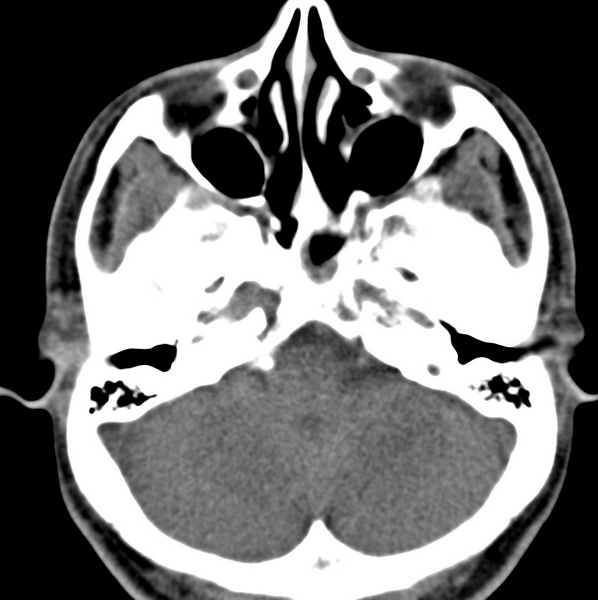

男、31、鼻咽部肿瘤放疗后请帮忙看看。

效果好,右侧破裂孔扩大,局部骨质缺损,为颅底骨质破坏。

1)鼻咽部肿瘤侵犯颅底放疗术后改变。2)左侧蝶窦炎。

咽后壁增厚,左侧咽鼓管隆突增大、咽鼓管咽口变浅,同侧咽旁间隙较窄。右侧颅底骨质破坏?为什么不在同一侧?

鼻咽部肿瘤侵犯颅底放疗术后改变.